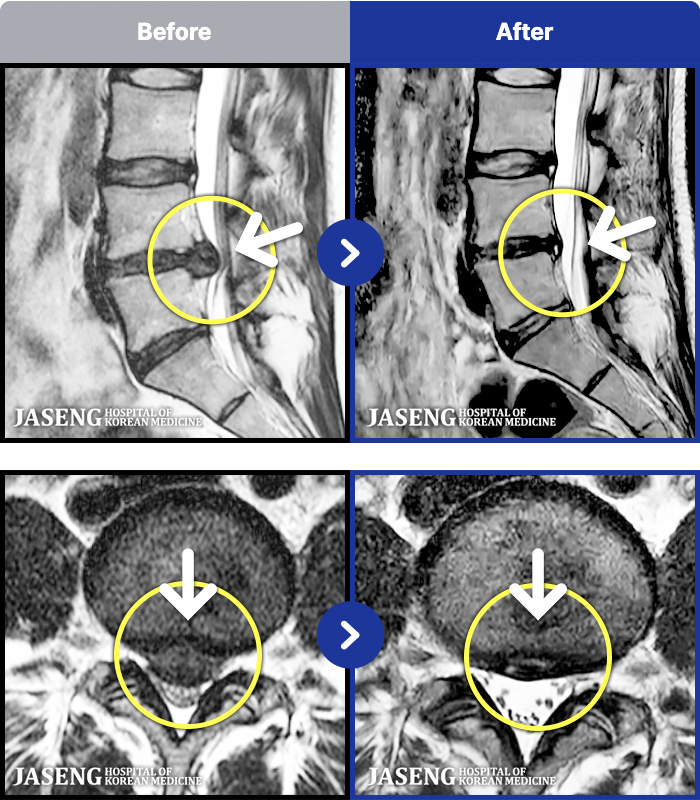

188 MRI ũ ʸ Ȯϼ.

ȯںп Ǹ ǿ ԿǾ, ο ġ ۿ Ƿ ġḦ Ͻñ ٶϴ.